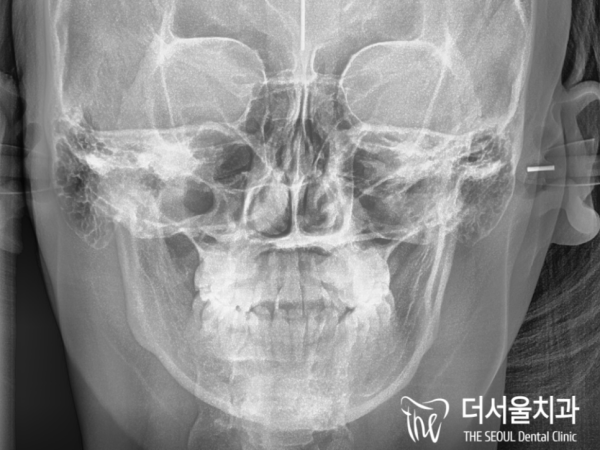

앞니 총생때문에 저희 성남치과 더서울치과를

찾아오셨다고 하셨는데요. 엑스레이 사진을 보아도

앞니 총생 말고는 다른 부분의 문제가 보이지는 않았습니다.

We went to Seongnam Dental Clinic and The Seoul Dental Clinic because of the total number of front teeth

You said you're here. Even if you look at the X-ray

I didn't see any problems other than the front tooth shooting.